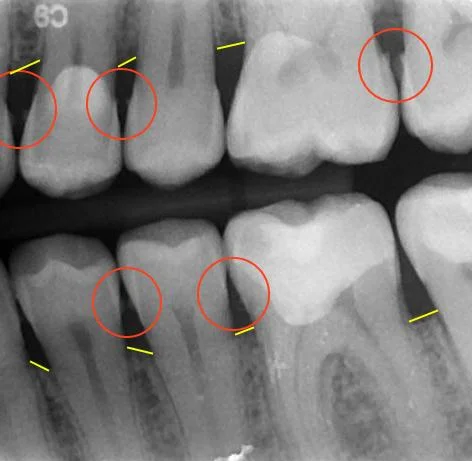

There are all sorts of elements that can help people make educated guesses that pertain to dental they do so in the midst of basic teeth cleaning sessions as well. The average cleaning costs $100. Who's the provider, and what all is included? What is difference between ct and cbct?